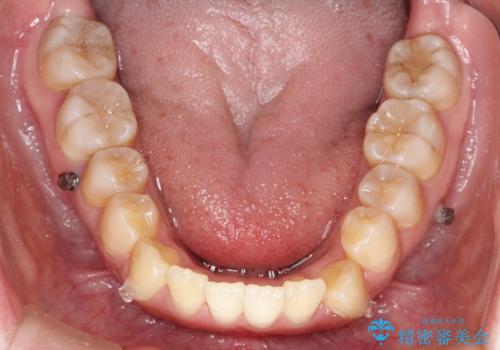

下顎の歯が、上顎の歯に対して前方に位置していたので、下顎の歯を後方に移動させるのと、歯と歯の間を削りスペースを作り、歯を並べる計画としました。

お仕事の関係で使用時間が制限されるときもあり、治療期間が予想より少し長くなりましたが、装置をつけずに治療を終えることができました。